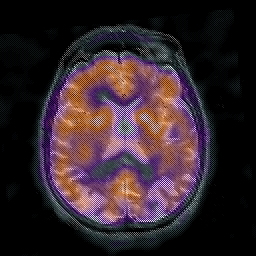

Alzheimer's disease: overlay -- Slice #31

[Home][Help][Clinical] Slice 31